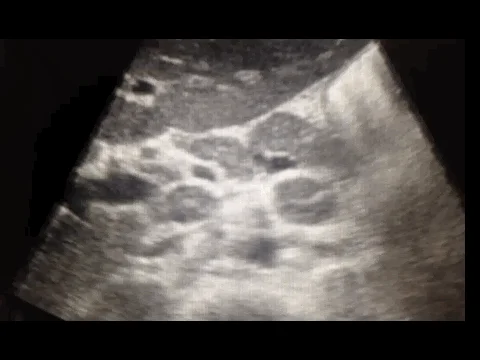

A 35 male year old patient in Malawi presents with 3 months of chronic night sweats, low grade fevers and weight loss. He has a history of HIV and on ART’s. His TB sputum smear test is negative and a chest x-ray is negative. You decide to perform a FASH exam. The following image is a transabdominal ultrasound, transverse of the midline.

Answer: B. Extrapulmonary Tuberculosis. The circular hypoechoic rings with hyperechoic borders and hyperechoic centers are abdominal lymph nodes, a finding present as part of the FASH protocol.

In extrapulmonary tuberculosis (TB), para-aortic lymph nodes can become enlarged due to infection. This is more commonly observed in patients who are immunocompromised, such as those with HIV. Sonographically, these lymph nodes usually appear hypoechoic and rounded due to loss of internal structures caused by caseous necrosis. The lymphadenopathy may be discrete, or nodes might be conglomerated into larger masses .

When using ultrasound to detect these nodes, they are visualized as hypoechoic structures, sometimes appearing to blink as the probe moves, distinguishing them from vessels that have consistent flow patterns. Enlarged nodes are typically over 1.5 cm in size in adults .

The presence of enlarged para-aortic lymph nodes in ultrasound, especially in the context of other findings such as splenic microabscesses, supports a diagnosis of abdominal TB in suspected cases.